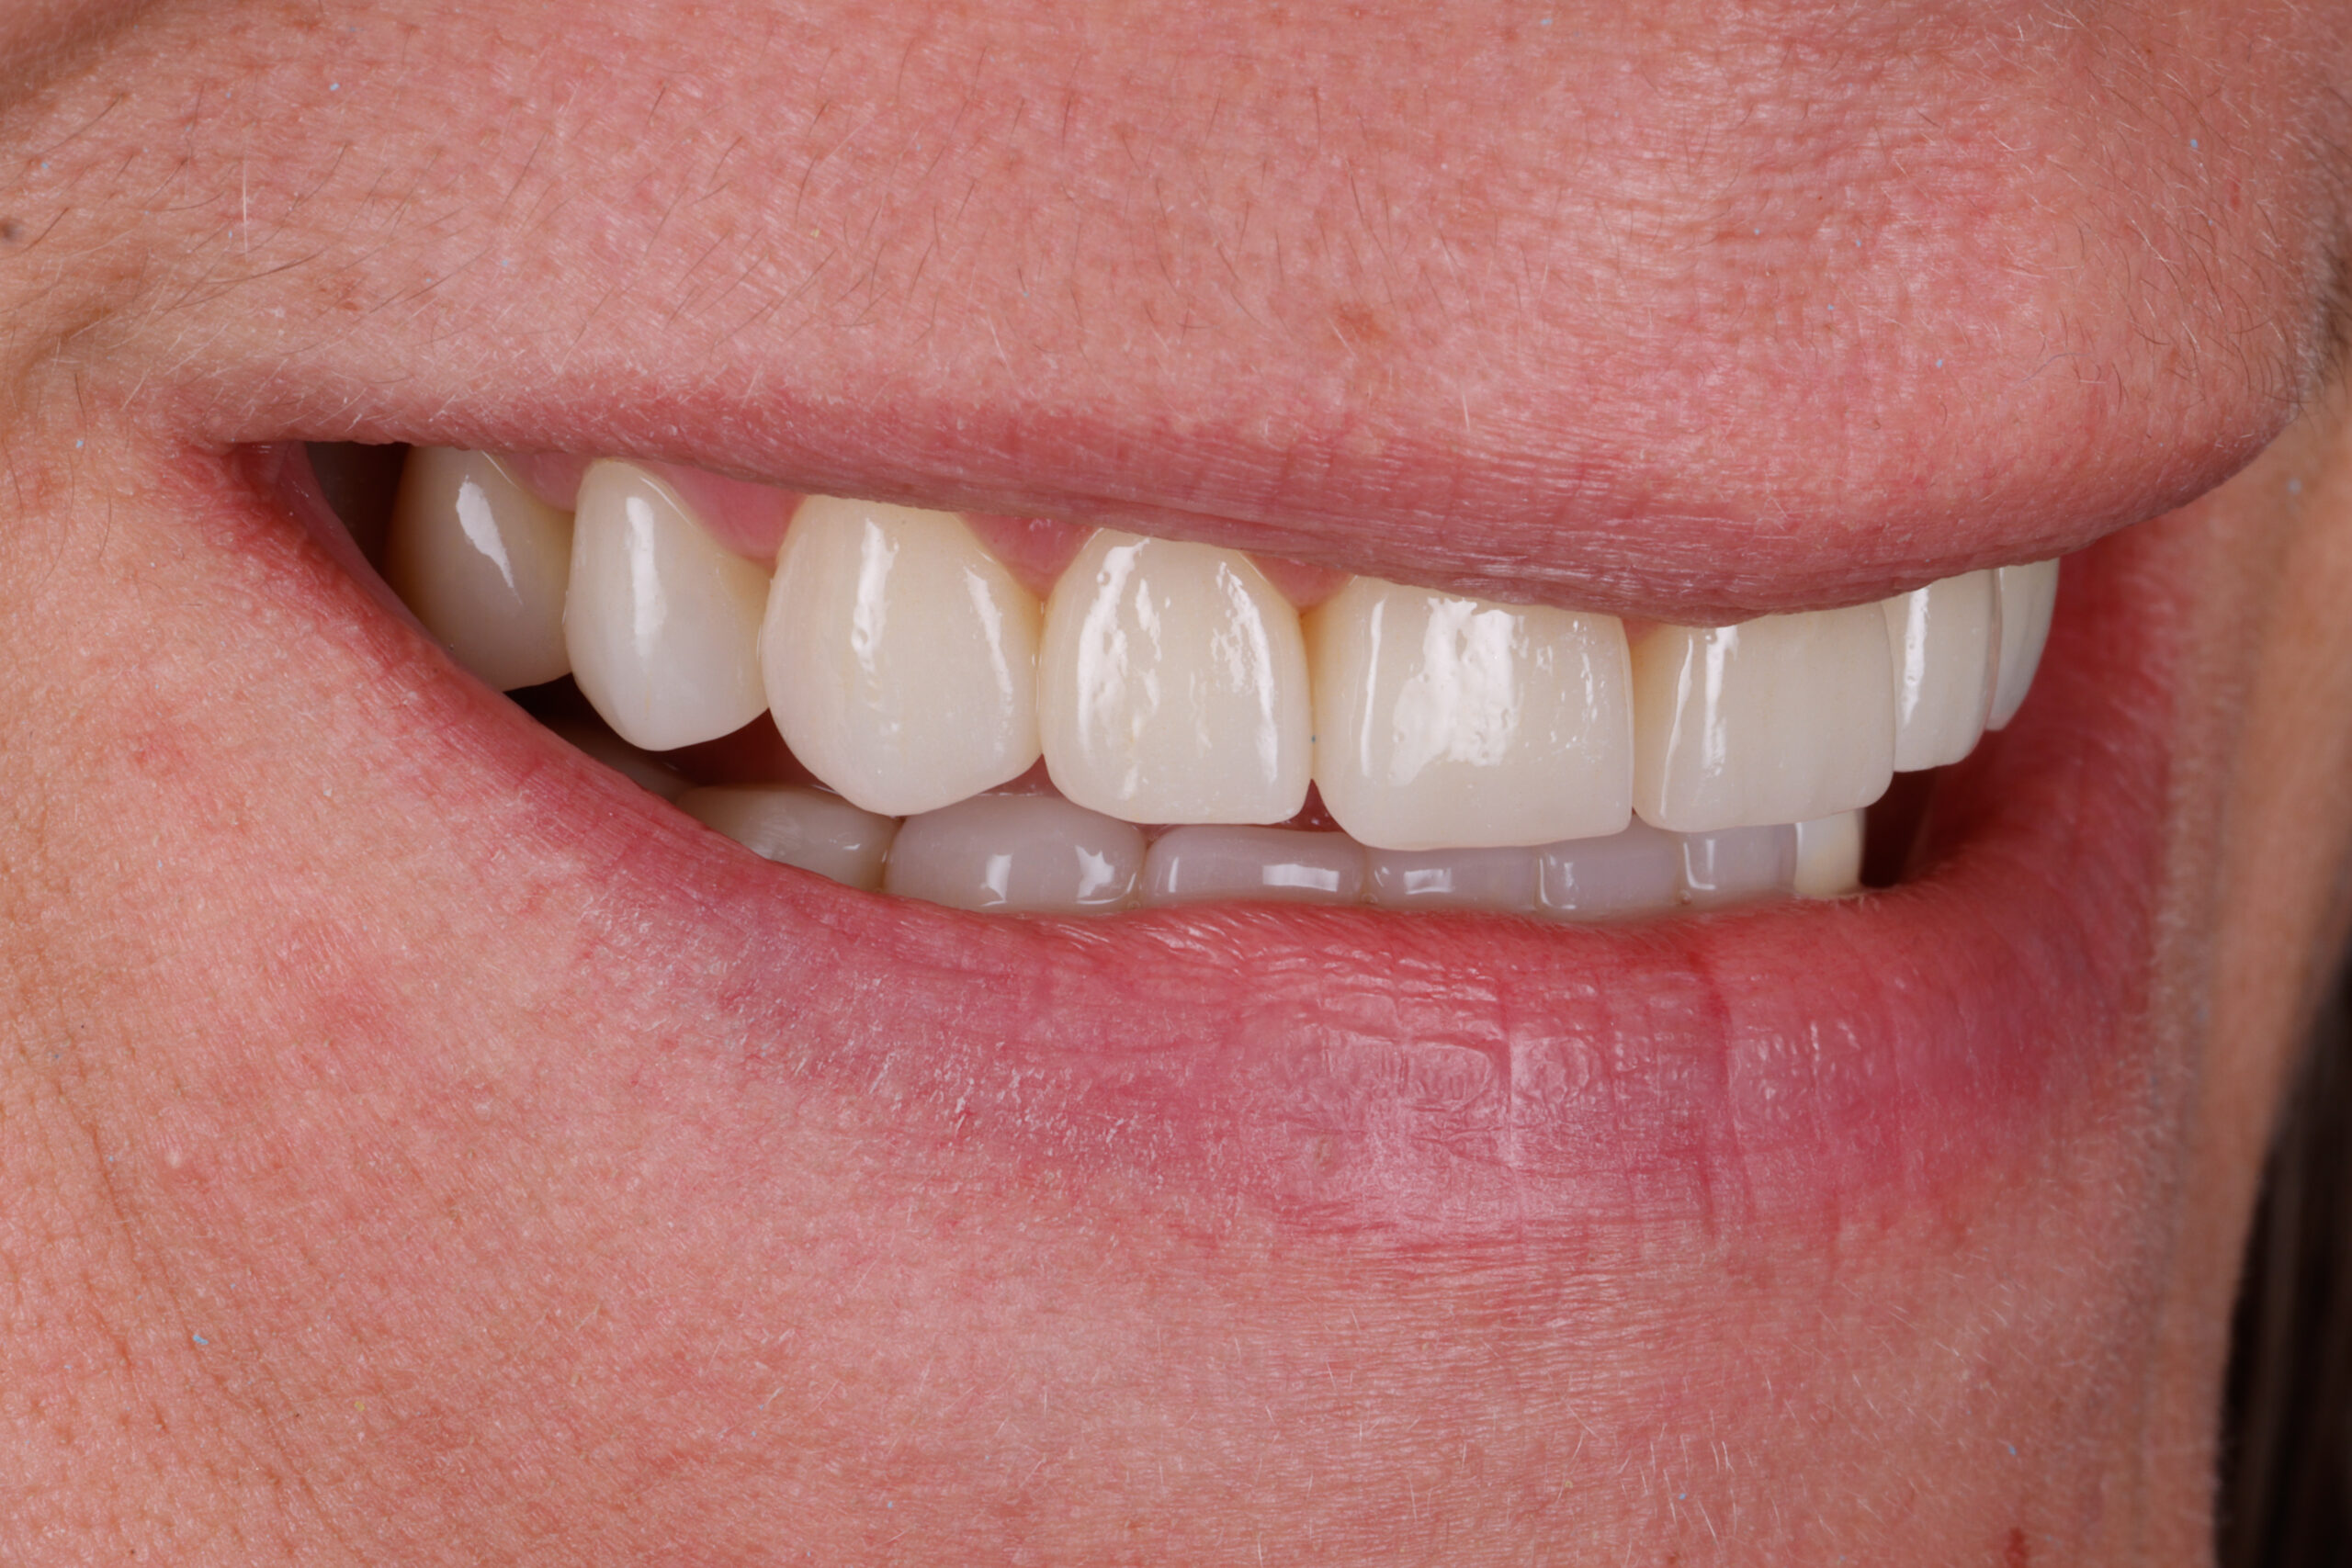

Before

After